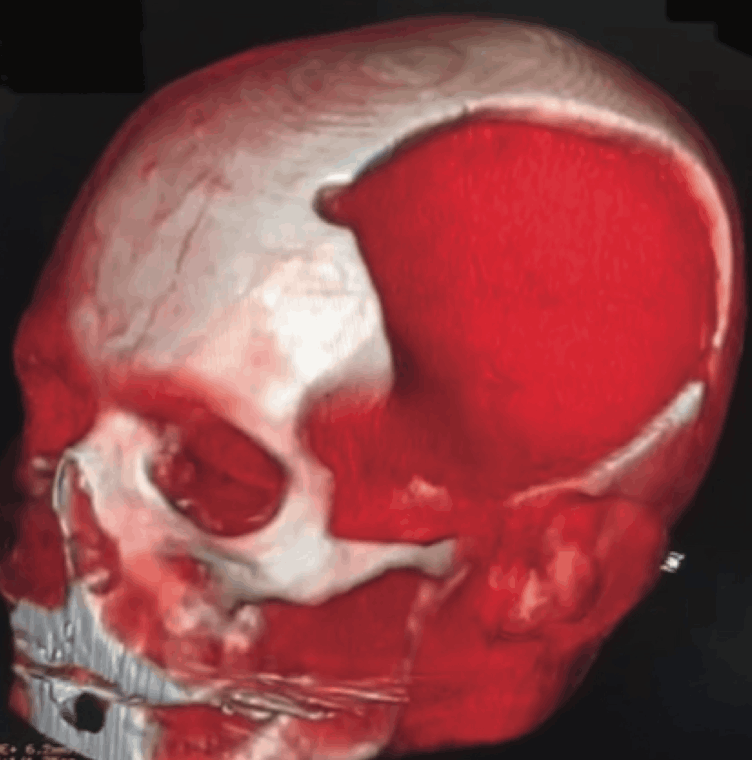

Cranioplasty For Treatment of Syndrome of The Trephined: Case Report And Literature Review.

Syndrome of the Trephined (ST) is a neurological complication observed after decompressive craniectomies, characterized by progressive neurological deterioration associated with the removal of a significant portion of the skull. ST is commonly seen in patients with severe traumatic brain injury, stroke, or other conditions that cause intracranial hypertension. Although rare, its clinical relevance is significant due to its impact on patient recovery.

The incidence of ST varies depending on the clinical context and region, with risk factors such as hemorrhagic injuries and brain displacement. In Brazil, the prevalence of the syndrome is underreported, partly due to the lack of large-scale studies, but its incidence has been increasing as decompressive craniectomies are more commonly performed in patients with severe intracranial hypertension.